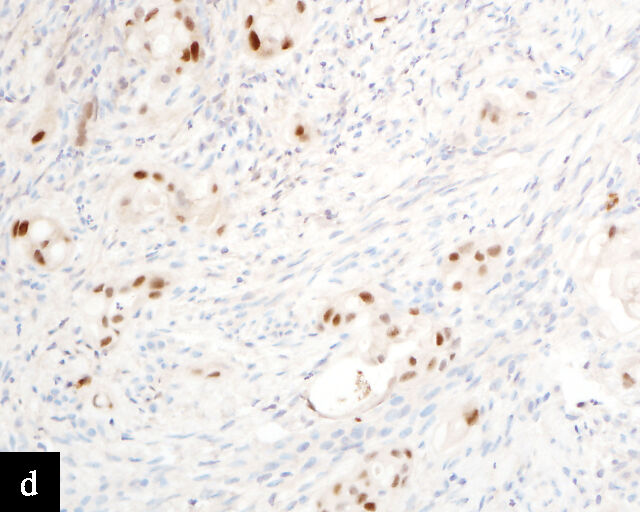

4

Gastric-type adenocarcinoma on cervical cytology.

In terms of epidemiology, HPV-associated precancerous lesions and HPV-associated cervical carcinomas are preventable by HPV vaccination,51 and decreases in incidence and mortality related to cervical carcinomas have been observed in regions in which effective population-level HPV vaccination has been adopted.52 As a result, the incidence of HPV-independent carcinomas is gaining increased clinical significance.53 Because these carcinomas are relatively uncommon and morphologically diverse, encompassing multiple morphologically distinct subtypes of adenocarcinomas with a wide variation in degree of differentiation,53 diagnosis by cervical cytology is challenging54 (Figure 4). Even so, cytomorphological assessment may allow the detection of HPV-independent cervical carcinomas, particularly morphologically high-grade tumors such as HPV-independent squamous cell carcinomas and clear cell adenocarcinomas.55 On the other hand, the absence of detectable precursor lesions on cytologic specimens, the subtle or non-HPV-related cytologic features of these tumors, and potential false reassurance from negative HPV testing can make HPV-independent adenocarcinomas more difficult to recognize microscopically. Consequently, the false-negative rate for cervical cytology in HPV-independent adenocarcinomas may be higher than that in HPV-associated adenocarcinomas.56